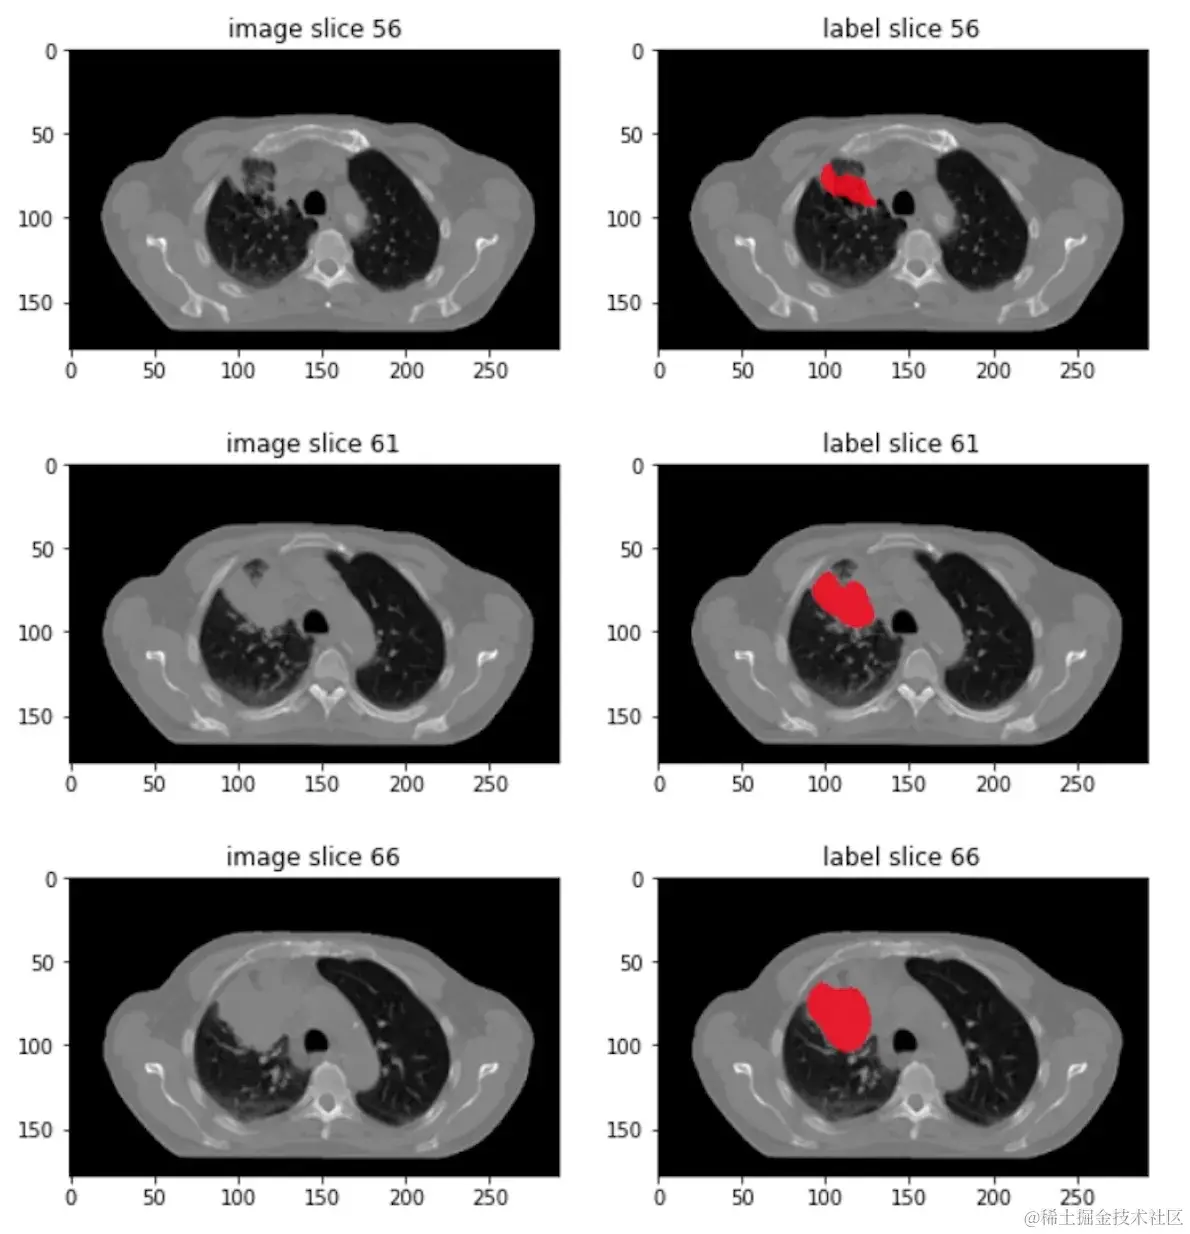

肿瘤分割任务

为了更好说明问题这里设置了一个场景,使用 Swin UNETR 模型从胸部 CT 扫描图像(单通道灰度 3D 图像)中分割肺部肿瘤。这是一个例子:

上述图片来源:wiki.cancerimagingarchive.net/display/Pub…

• 左栏显示了 3D CT 扫描图像在轴向平面上的一些 2D 切片。两个新月形的黑色区域是肺部。

• 右栏显示肺部肿瘤的手动标注。

胸部 CT 扫描的大小通常为 512×512×300,大约需要 6090 兆字节存储在磁盘中。它们不是小图像。